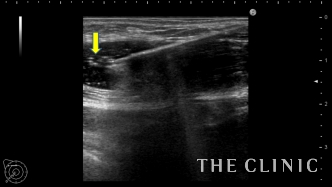

ヒアルロニダーゼが入ると加水分解して白く点状の画像として描出されます。

しこり全体にヒアルロニダーゼが浸透するように十分な量を注入することがポイントです。

ヒアルロニダーゼを注入すると容易にヒアルロン酸を吸引除去することができます。

吸引をしっかり行い、エコー上はすべて消失しました。